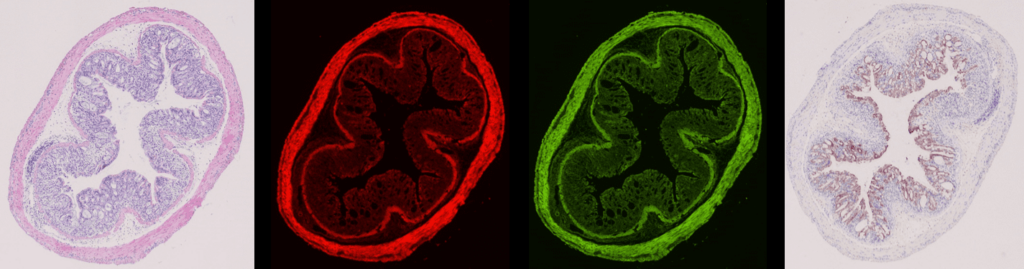

動物都會患上癌症,當中以淋巴癌為貓狗最常見的腫瘤之一。香港城市大學物理學系副教授劉康德領導的初創公司創新進領(ITsci),運用數碼醫學成像技術結合人工智能(AI),成功開發了「AI染色」技術,協助獸醫診斷貓狗淋巴瘤細胞。這項「AI染色」技術有望取代緩慢、昂貴及難以使用的抗體染色,團隊更展望未來將此技術應用於人類乳癌的診斷。

香港城市大學物理學系副教授及創新進領有限公司創辦人劉康德帶領團隊研發人工智能染色系統。獸醫只需以微針抽取動物血液或其他體液樣本,再以電腦存取數碼顯微鏡樣本影像後,透過結合數碼化醫學成像技術的AI系統「AIstain」,並以「蘇木精—伊紅染色法」(H&E)染色。

AI系統「AIstain」僅需用一塊組織便能製作多個虛擬染色圖,減少樣本需求,最快於幾分鐘內有結果,有助縮短等侯診斷報告的時間;加上改善採樣方式以微針抽取動物血液或其他體液樣本,免卻動物承受切片抽組織的風險。

團隊自2018年起已試驗約100個樣本,取得了幾億粒細胞資料,其準確率可達到95%以上。

AI染色於雲端執行,不需使用專門設備,這意味各地病理學家只需數碼顯微鏡和連接互聯網的電腦即可使用此技術。劉康德說:「現在化驗有可能做幾種染色,所以要切數塊組織樣本。每一塊只可以染色一次,這個技術的優勢是可以一塊組織做數個虛擬染色,簡化程序、減少樣本需求。可以幾分鐘內得到同一個效果,因為他網上做,化驗所不需要有特設染色設備。」